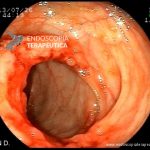

- Doença de Crohn em remissão – cicatriz